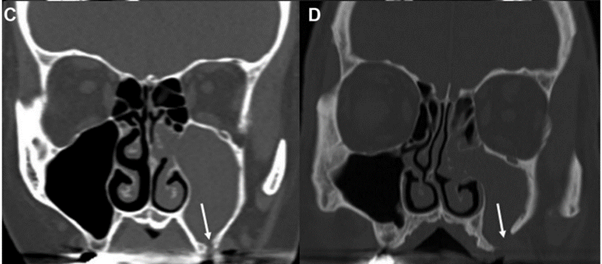

白箭头指示上颌窦牙龈瘘

3)口腔上颌窦瘘是指口腔和上颌窦之间的病理性、非自然通道;

鼻内镜检查单侧中鼻道脓性物(下图)

中鼻道脓性物流向鼻咽部